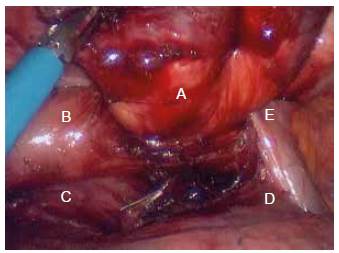

Mujer de 72 años de edad, con cuadro clínico de un año de disfagia y atragantamiento con alimentos sólidos, que había requerido tratamiento endoscópico. Se realiza endoscopia de vías digestivas altas que documenta un divertículo esofágico en tercio medio, y manometría esofágica de alta resolución, sin trastorno motor. El esofagograma (figura 1) y la tomografía computarizada de tórax (figura 2) muestran un divertículo en tercio medio de esófago, lateral derecho, de 7 cm de diámetro y base de 2.5 cm de diámetro. De manera programada se lleva a cabo diverticulectomía esofágica por toracoscopia, en decúbito prono (figura 3), sin complicaciones.

Los divertículos esofágicos son una patología infrecuente, con una prevalencia de 0,06 - 4 % 1-4. Suelen ser asintomáticos, pero en caso contrario, el síntoma más frecuente es la disfagia 2-4. Los divertículos esofágicos del tercio medio se forman por mecanismo de tracción, y se asocian a procesos inflamatorios crónicos del mediastino, fibrosis y trastornos motores del esófago, en un 90 % de los casos; sin embargo, se desconoce si el trastorno motor es primario o secundario a la presencia del divertículo 1,2,4. Puesto que suelen ser asintomáticos, el diagnóstico es habitualmente incidental mediante esofagograma u otras pruebas radiológicas o endoscópicas, y no precisan tratamiento 1-4. No obstante, ante la presencia de síntomas, el tratamiento de elección es la resección quirúrgica por toracoscopia o toracotomía 2-4.